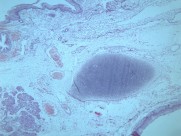

一般认为畸胎瘤多系个体发育初期,部分多能性原始细胞迷离出来,在纵隔内增殖发展成肿瘤。这类肿瘤以良性畸胎瘤多见。常位于前纵隔。畸胎瘤多为实质性,可同时存在大小不等的囊腔,内含外、中或内胚层组织的衍生物如毛发、牙齿、软骨、平滑肌、支气管或肠壁等。部分畸胎瘤可以恶变。由未分化成熟组织构成的畸胎瘤属恶性,呈浸润性生长。畸胎瘤与邻近组织粘连或穿破入邻近脏器如肺、支气管,病人可咳出毛发或皮脂样物。皮样囊肿是一种单房或多房薄壁囊肿,因囊内多衬以鳞状上皮及其附属物而得名。囊内有结节状物、毛发及皮脂类物。